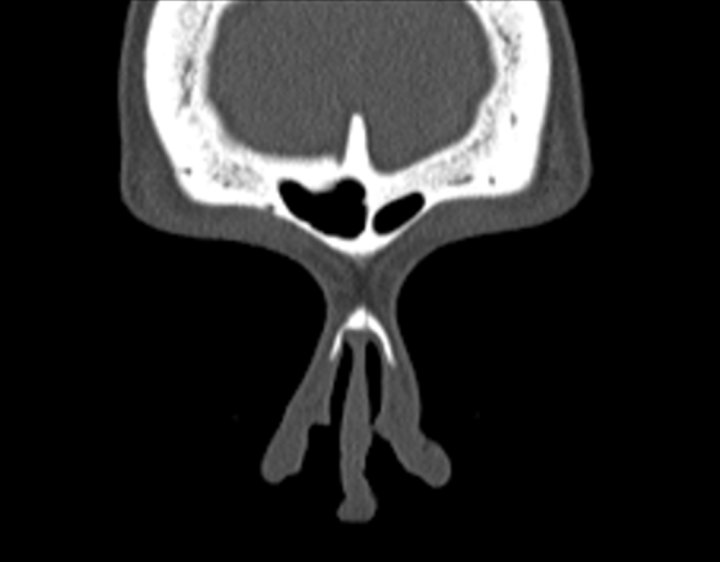

Click any image for labels.